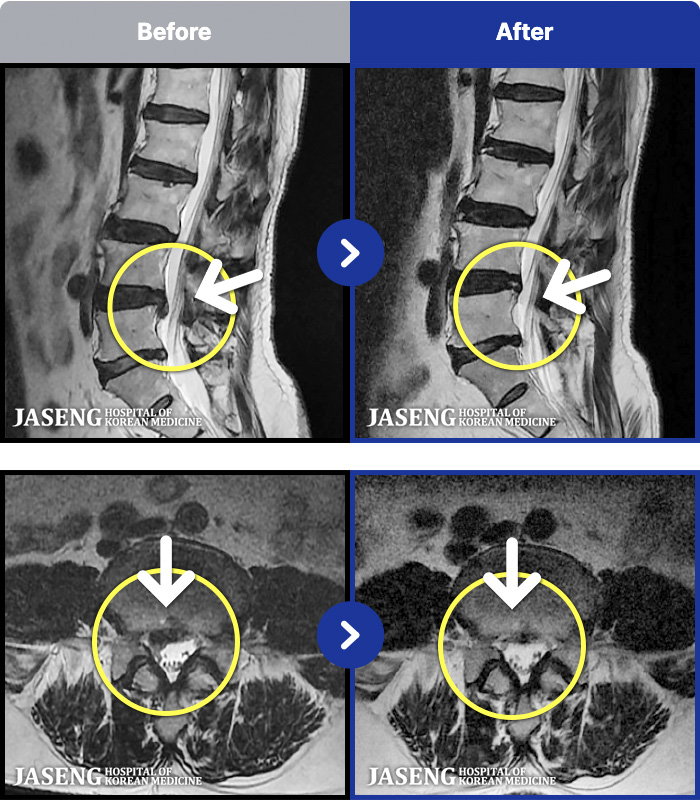

MRI ġ

129 MRI ũ ʸ Ȯϼ.

Ƹ ϰ ־.

[õ] 25.03.18~25.07.22

ȯںп Ǹ ǿ ԿǾ, ο ġ ۿ Ƿ ġḦ Ͻñ ٶϴ.